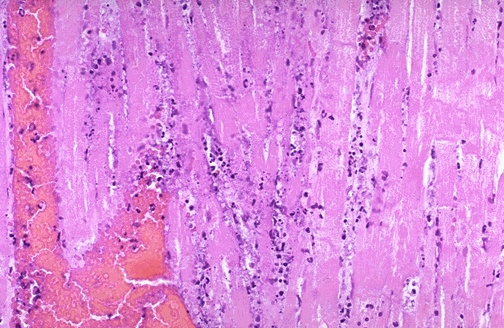

Image 2.4

Later, the myocardium has the microscopic appearance shown here.